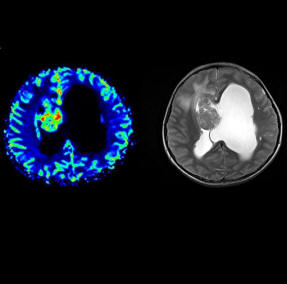

syngo ASL (Arterial Spin Labeling) 2D: Arterial Spin

Labeling (ASL) is an MR technique using the water in

arterial blood as an endogenous contrast agent to

evaluate perfusion noninvasively.

syngo ASL provides unique insight into human brain

perfusion and function physiology by evaluating cerebral

blood flow. syngo ASL is capable of high spatial

resolution perfusion imaging, making the technique very

appealing in the evaluation of stroke, tumors,

degenerative diseases, epilepsy but also in basic

neuroscience, e.g. for studies of functional CBF

syngo ASL (Arterial Spin Labeling) 3D: Arterial Spin

evaluate perfusion noninvasively. syngo ASL provides

unique insight into human brain perfusion and function

by evaluating cerebral blood flow. syngo ASL is capable

of high spatial resolution perfusion imaging, making the

technique very appealing in the evaluation of stroke,

tumors, degenerative diseases, epilepsy but also in

basic neuroscience, e.g. for studies of functional CBF

changes.